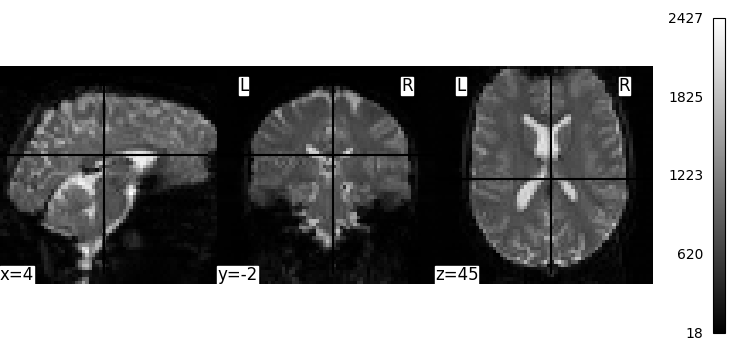

We can display the mean functional image and the subject’s anatomy:

from nilearn.image import mean_img

from nilearn.plotting import plot_anat, plot_img, plot_stat_map, show

fmri_img = subject_data.func

mean_img = mean_img(subject_data.func[0])

plot_img(mean_img, cbar_tick_format="%i")

plot_anat(subject_data.anat, cbar_tick_format="%i")

show()